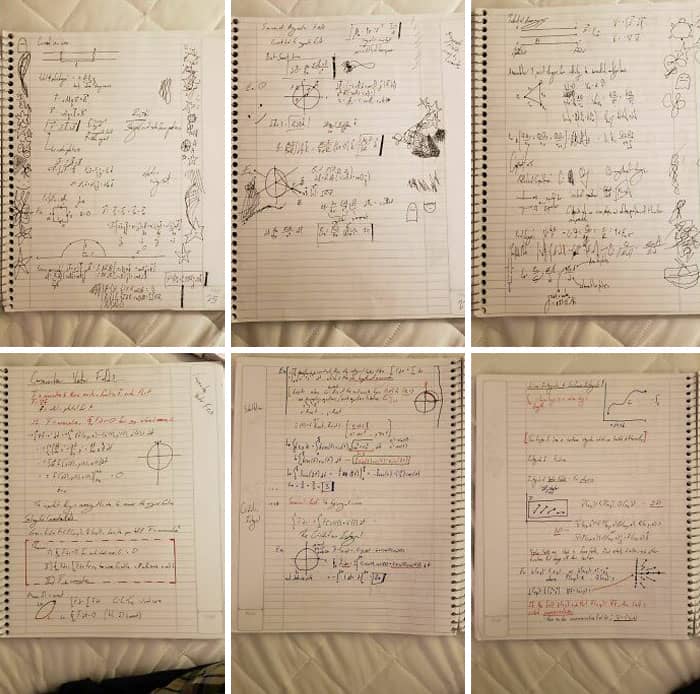

#24 My Notes Before And After Being Prescribed Adderall